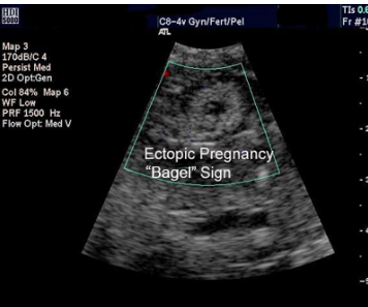

Describe ultrasound findings of an ectopic pregnancy [2]

A

1. ID a gestational sac containing a yolk sac or fetal pole in fallopian tube / not intrauterine

2. Mass representing a tubal ectopic pregnancy moves separately to the ovary

3. ID empty uterus

4. Fluid in the uterus: pseudo-gestational sac

5. sometimes described as a ‘tubal ring’ or ‘bagel sign’: